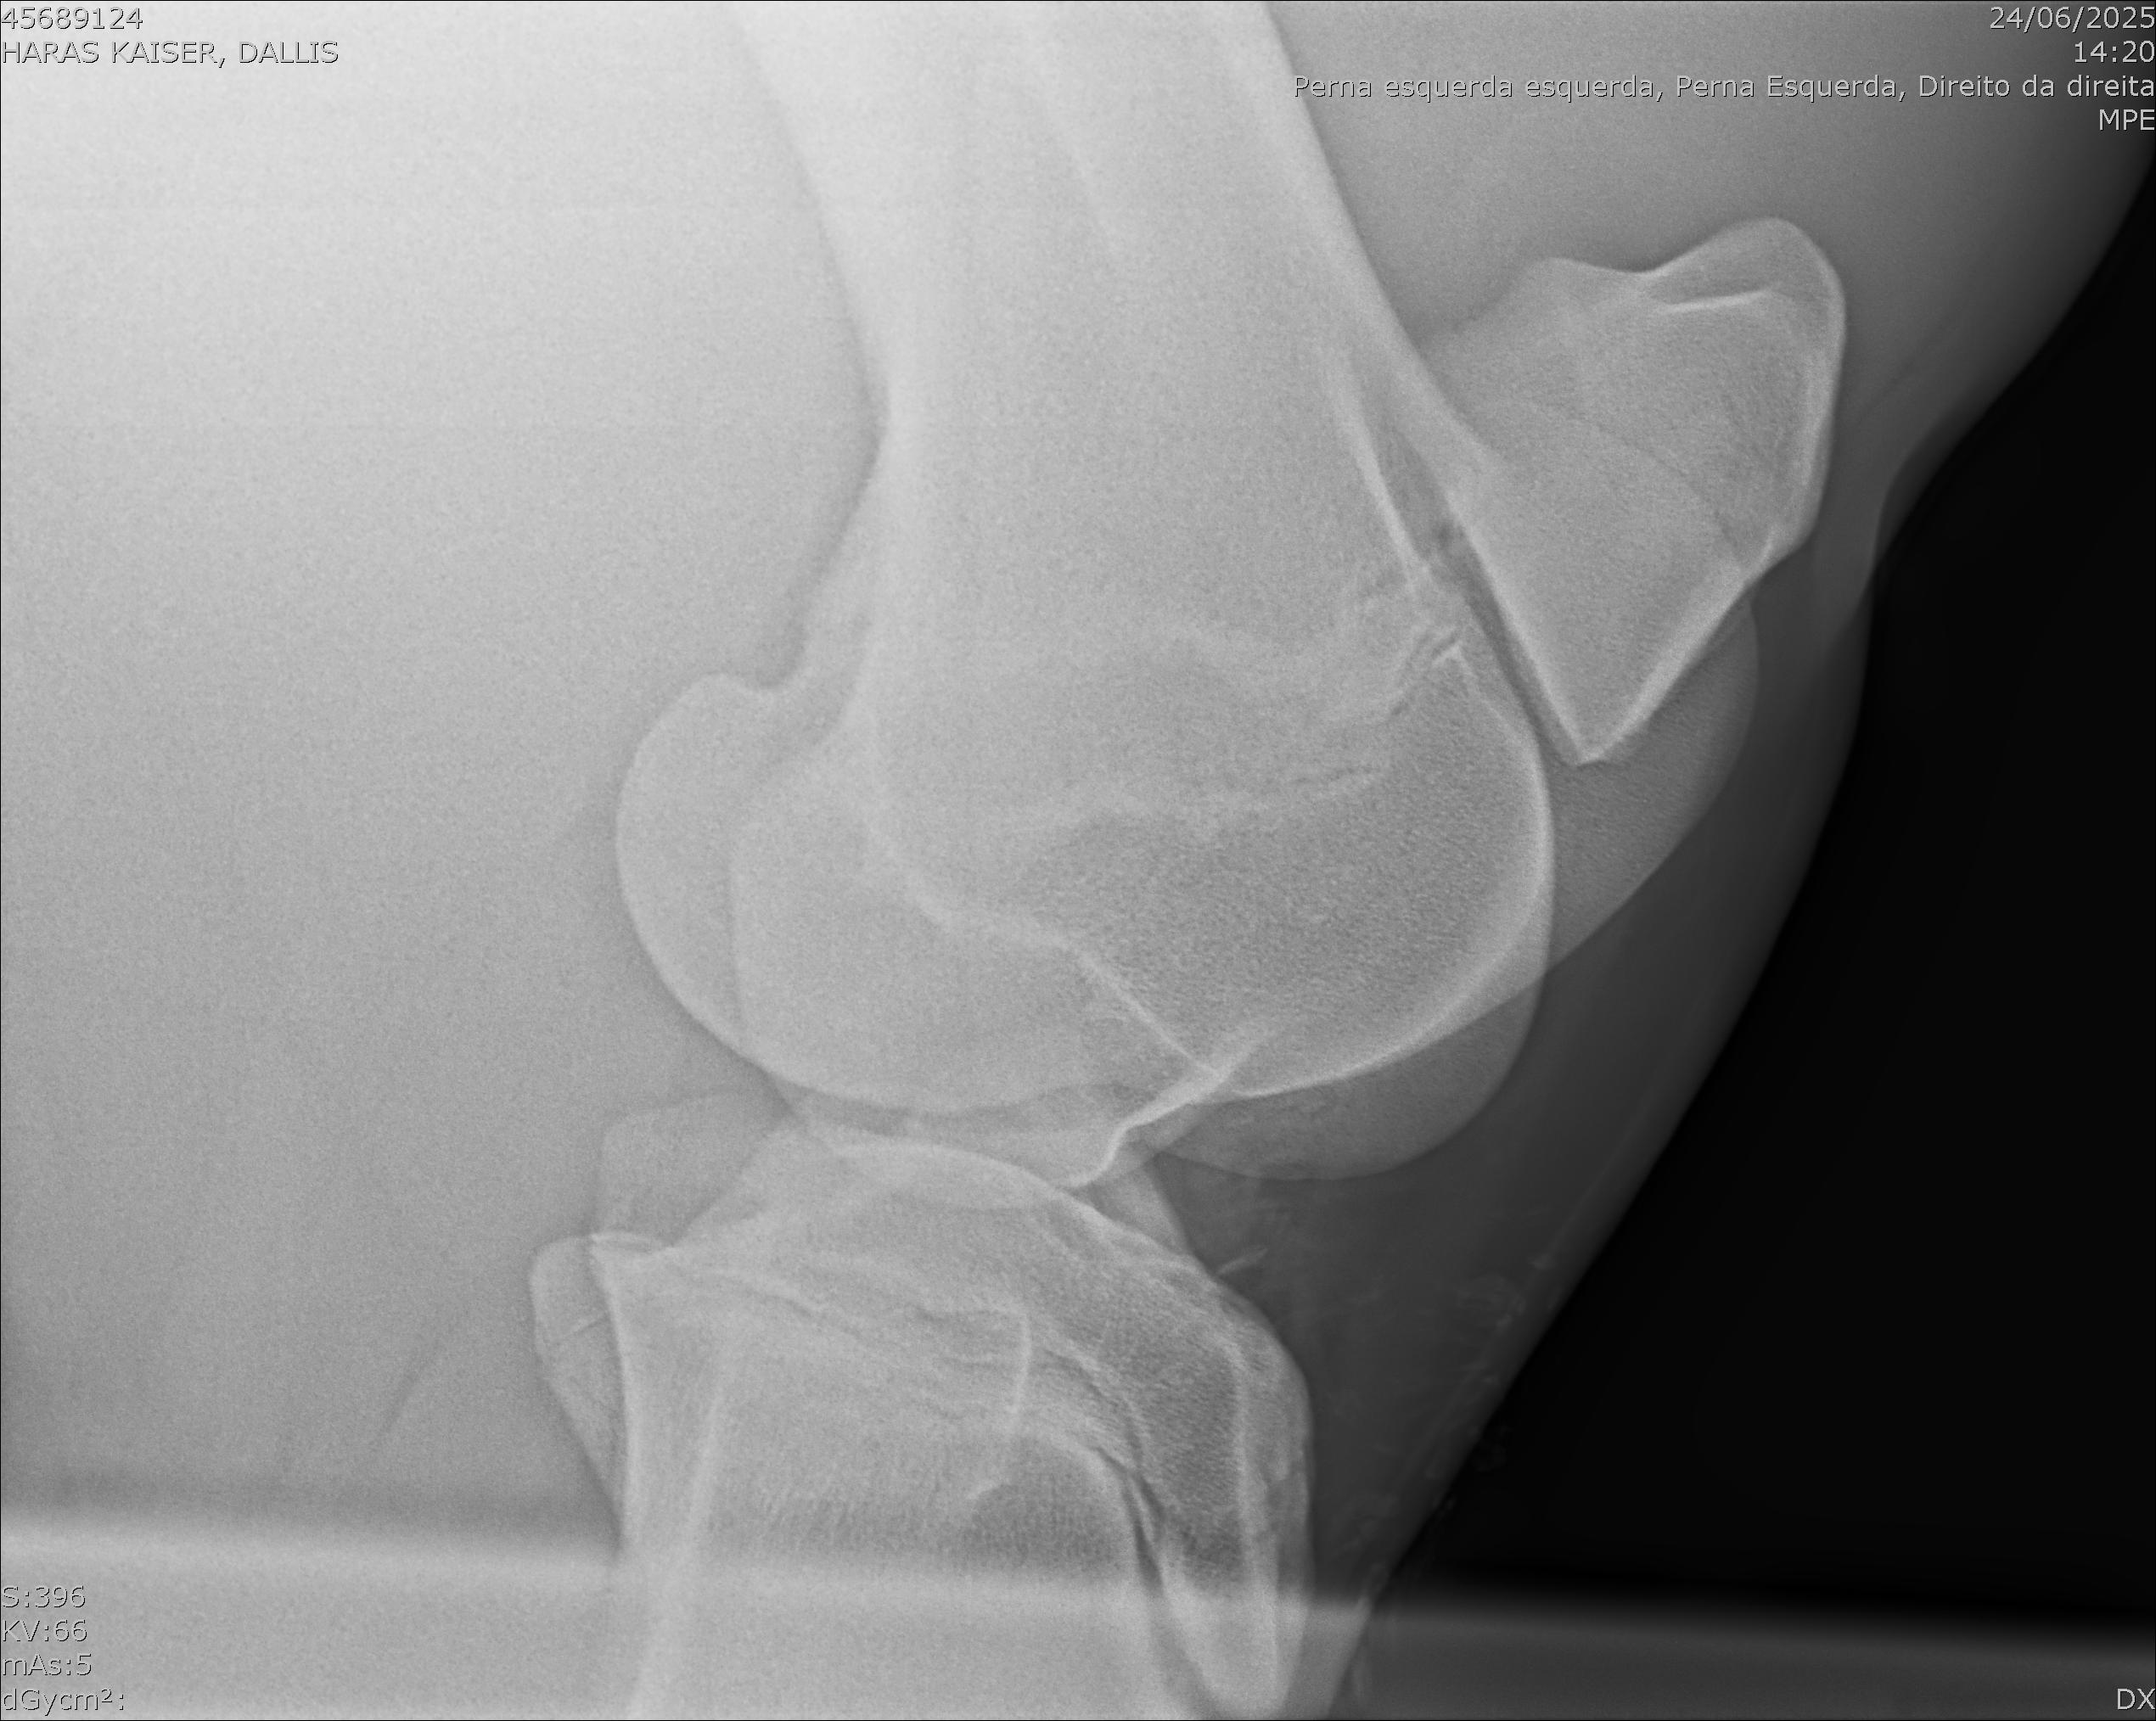

:: RAIOS-X DO LOTE